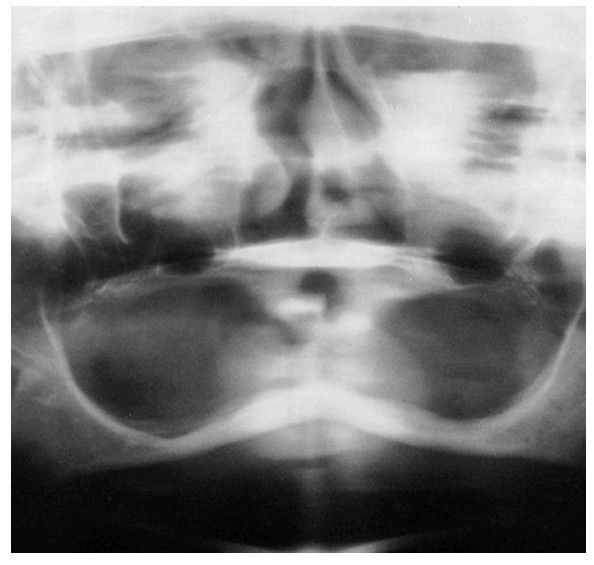

Radiograph demonstrating atrophic mandibular and maxillary alveolar ridges. Pneumatization of the maxillary sinus is demonstrated